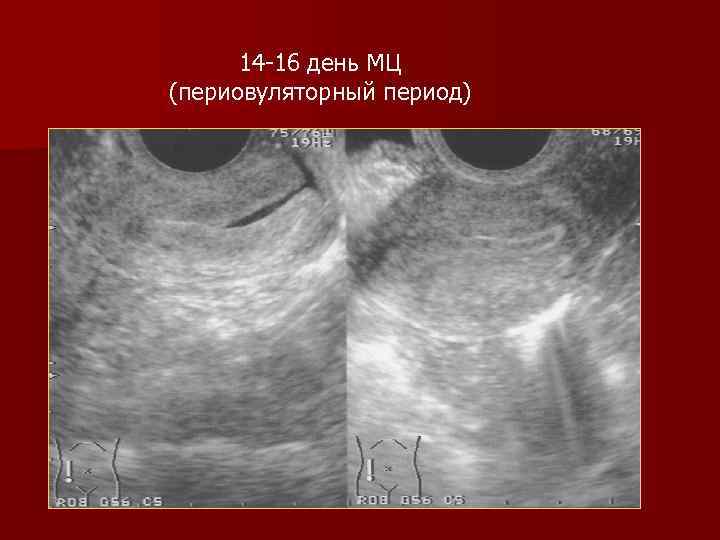

14 -16 день МЦ (периовуляторный период)